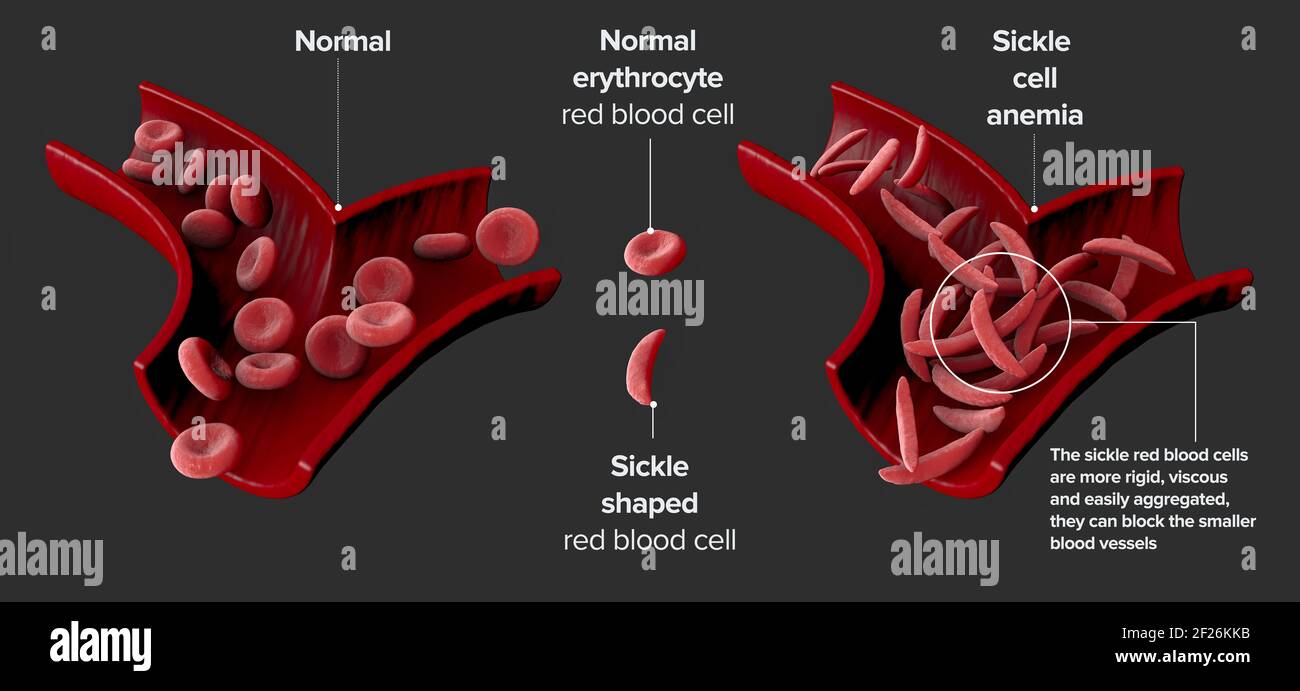

Sickle cell disease is a group of blood disorders. Sickle cell anaemia. It results in an abnormality in the oxygen-carrying protein haemoglobin Stock Photohttps://www.alamy.com/image-license-details/?v=1https://www.alamy.com/sickle-cell-disease-is-a-group-of-blood-disorders-sickle-cell-anaemia-it-results-in-an-abnormality-in-the-oxygen-carrying-protein-haemoglobin-image414430313.html

Sickle cell disease is a group of blood disorders. Sickle cell anaemia. It results in an abnormality in the oxygen-carrying protein haemoglobin Stock Photohttps://www.alamy.com/image-license-details/?v=1https://www.alamy.com/sickle-cell-disease-is-a-group-of-blood-disorders-sickle-cell-anaemia-it-results-in-an-abnormality-in-the-oxygen-carrying-protein-haemoglobin-image414430313.htmlRF2F26X2H–Sickle cell disease is a group of blood disorders. Sickle cell anaemia. It results in an abnormality in the oxygen-carrying protein haemoglobin

Sickle cell disease is a group of blood disorders. Sickle cell anaemia. It results in an abnormality in the oxygen-carrying protein haemoglobin Stock Photohttps://www.alamy.com/image-license-details/?v=1https://www.alamy.com/sickle-cell-disease-is-a-group-of-blood-disorders-sickle-cell-anaemia-it-results-in-an-abnormality-in-the-oxygen-carrying-protein-haemoglobin-image414425295.html

Sickle cell disease is a group of blood disorders. Sickle cell anaemia. It results in an abnormality in the oxygen-carrying protein haemoglobin Stock Photohttps://www.alamy.com/image-license-details/?v=1https://www.alamy.com/sickle-cell-disease-is-a-group-of-blood-disorders-sickle-cell-anaemia-it-results-in-an-abnormality-in-the-oxygen-carrying-protein-haemoglobin-image414425295.htmlRF2F26KKB–Sickle cell disease is a group of blood disorders. Sickle cell anaemia. It results in an abnormality in the oxygen-carrying protein haemoglobin